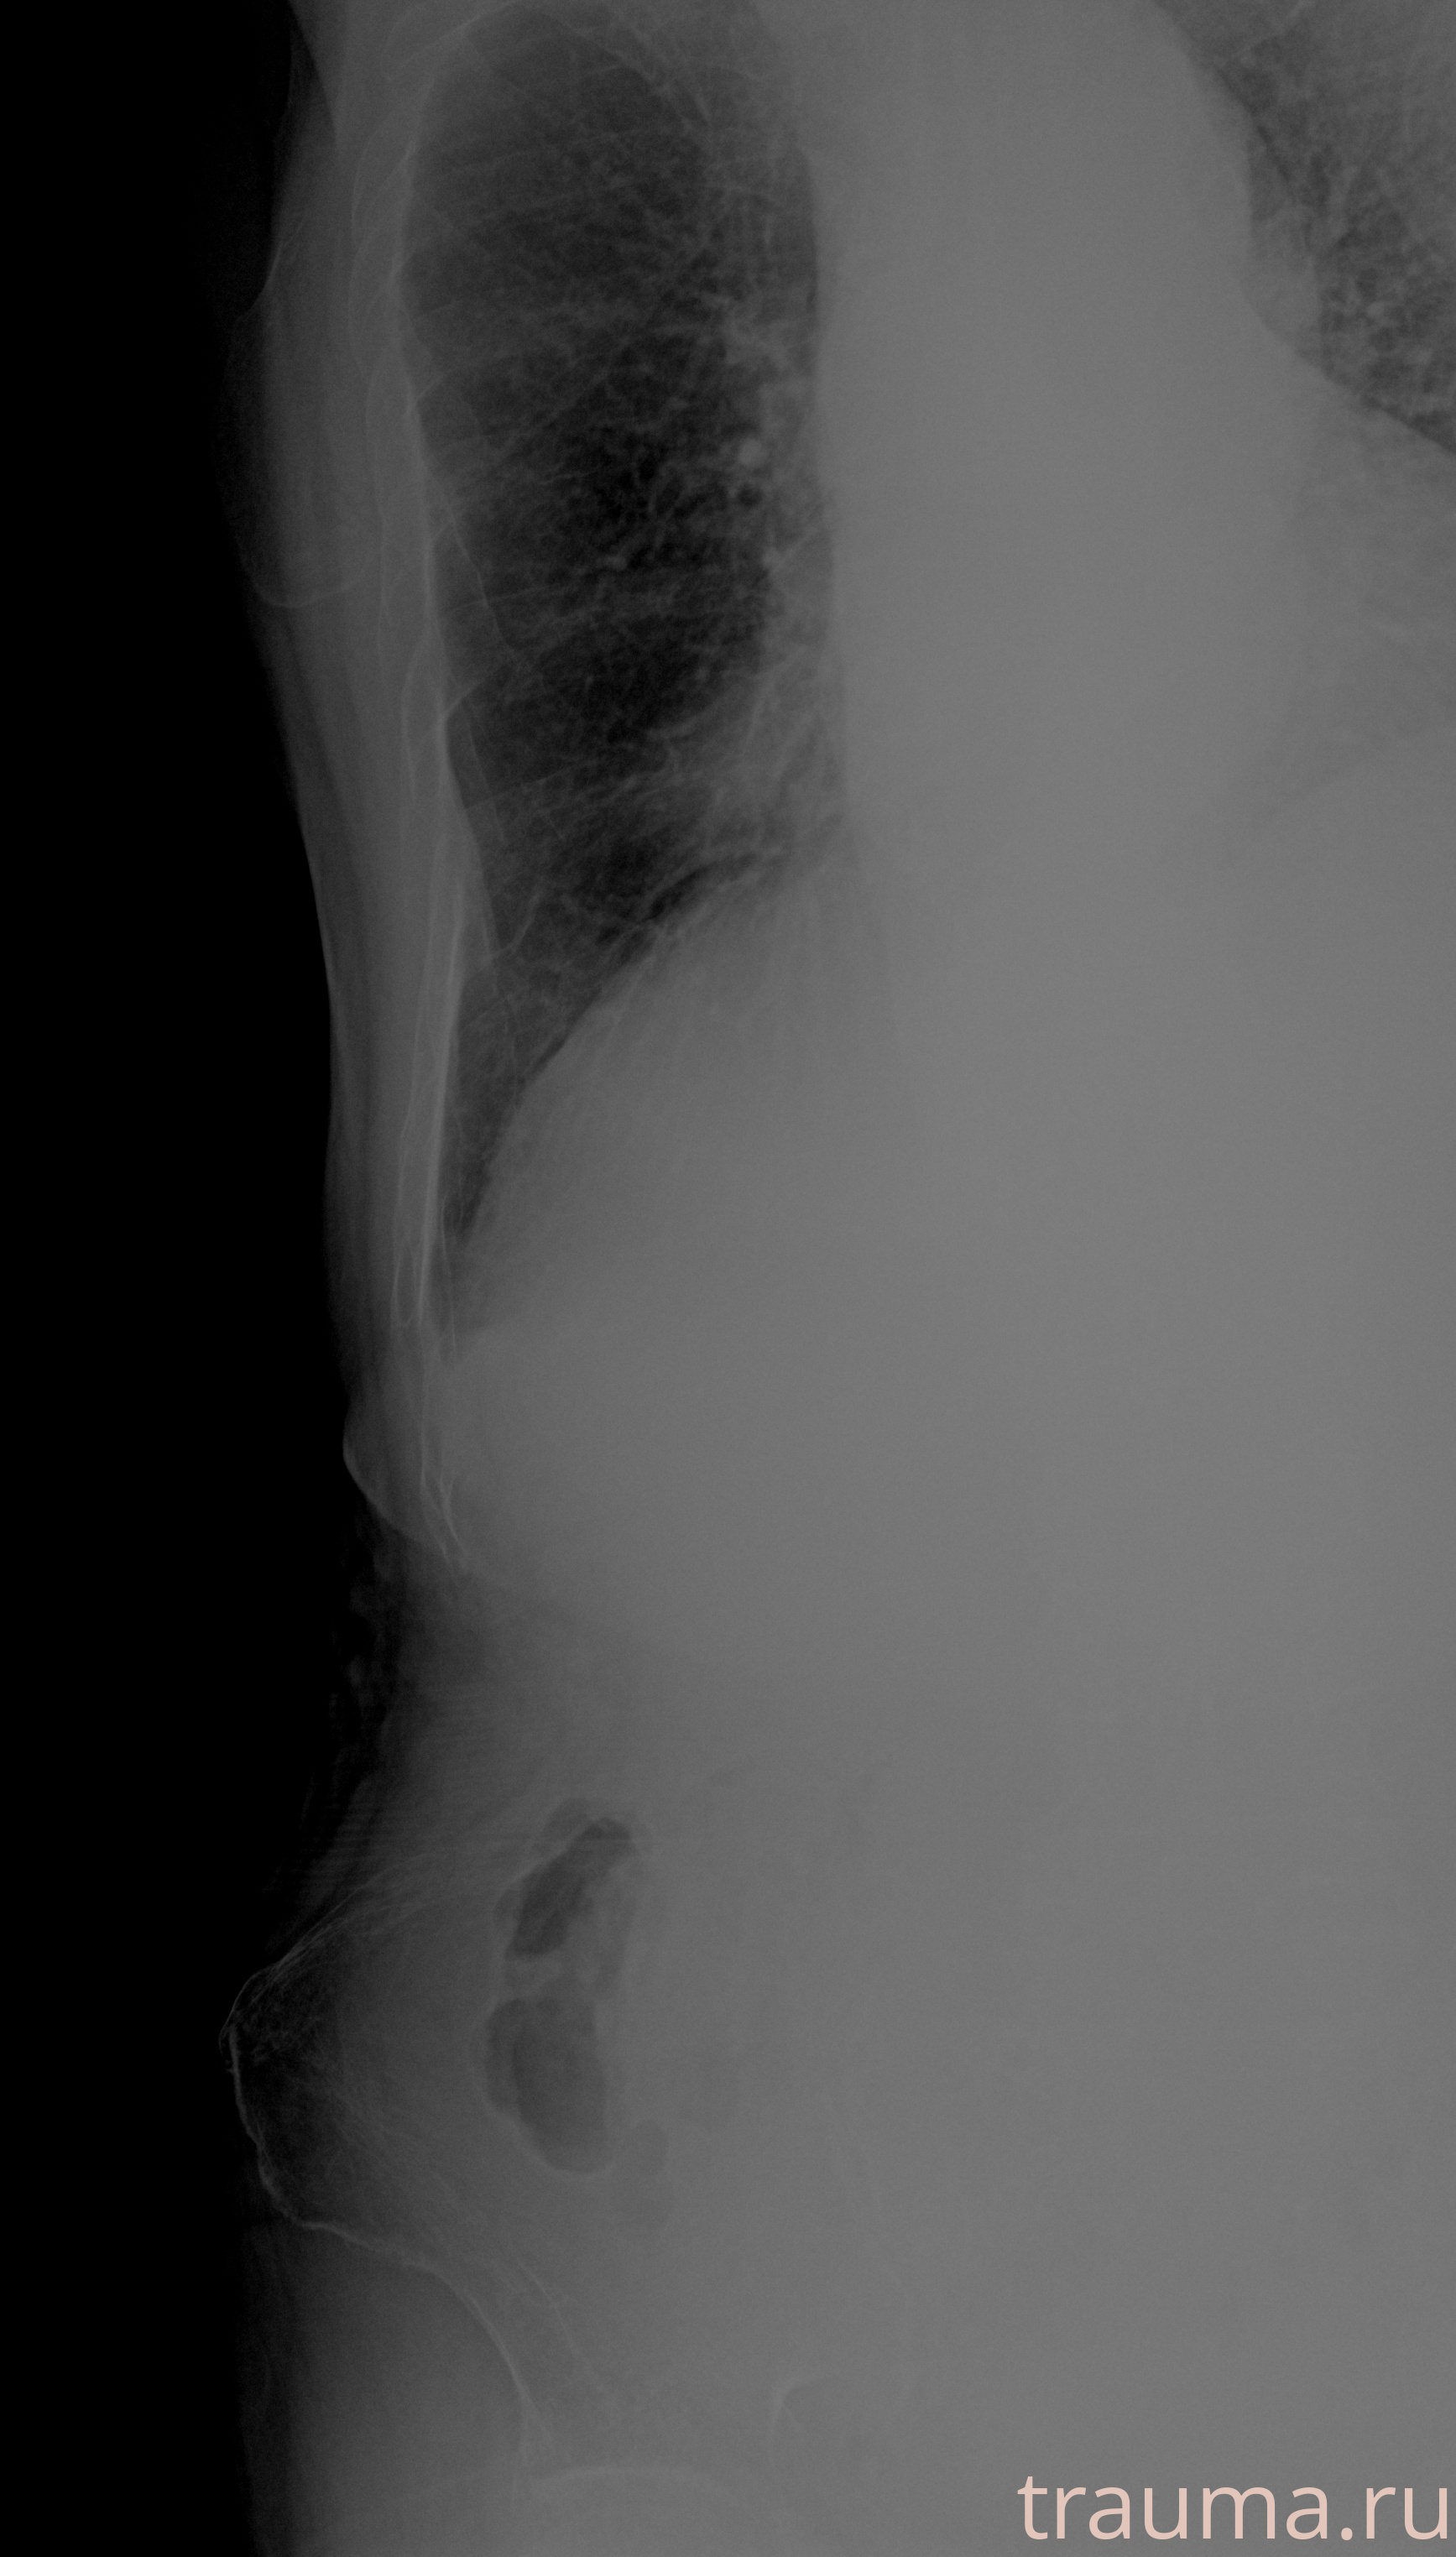

Рентгенограммы

Рентген на дому: по вашему адресу приезжает врач-рентгенолог, травматолог-ортопед с мобильным рентгеновским аппаратом, проводит диагностику травмы или заболевания, делает необходимые рентгенограммы, дает рекомендации по дальнейшему лечению. Получить качественные снимки в домашних условиях возможно благодаря уникальной методике, разработанной МосРентген Центром для института  Склифосовского

при переломе шейки бедра и пневмонии от компании МосРентген Центр - партнера Института имени Склифосовского